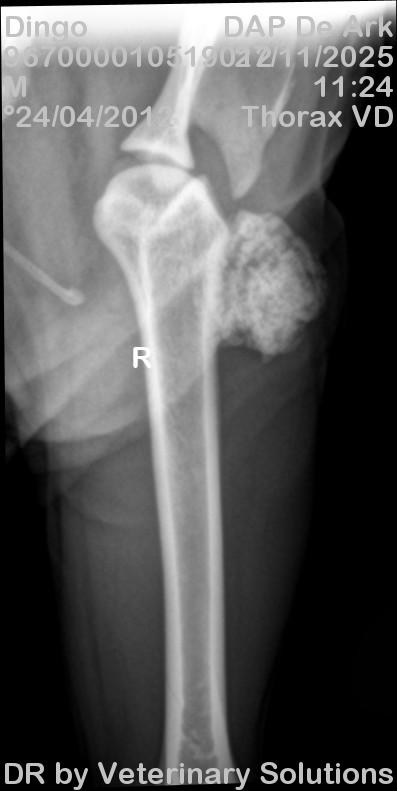

Tijdens het lichamelijk onderzoek werd een harde, niet verplaatsbare massa gepalpeerd ter hoogte van de laterale zijde van de humerus. Naar aanleiding van deze bevinding werd een radiografie uitgevoerd. Hierop was een massa met botopaciteit zichtbaar aan de laterale zijde van de proximale humerus (zie bijgevoegde RX). Biopsie werd ingepland en histopathologisch onderzoek bevestigde de diagnose van een laaggradig chondrosarcoom.

Chondrosarcomen zijn zeldzame neoplasieën bij de kat en ontstaan uit kraakbeenweefsel. Ongeveer twee derde van de gevallen ontstaat ter hoogte van de lange beenderen, waarbij mankheid vaak de belangrijkste klinische klacht vormt. Andere voorkomende lokalisaties zijn de platte beenderen, zoals de schedel, ribben, sternum, bekken en scapula, evenals subcutane weefsels waar de tumor zich presenteert als een onderhuidse massa.

Hoewel chondrosarcomen relatief snel lokaal kunnen groeien, is de kans op metastasering bij de kat beperkt. Hierdoor kan een chirurgische behandeling in veel gevallen curatief zijn, zeker wanneer de tumor volledig kan worden verwijderd.

De voorkeursbehandeling van chondrosarcoom bij de kat bestaat uit chirurgische verwijdering met ruime marges. Hierbij wordt niet alleen de zichtbare massa verwijderd, maar ook een voldoende hoeveelheid omliggend gezond weefsel om het risico op lokaal recidief te beperken. In het geval van een bottumor ter hoogte van een lidmaat wordt doorgaans een amputatie van het aangetaste lidmaat aanbevolen.

De eigenaars besloten geen chirurgie bij Dingo uit te voeren, maar hem palliatief met pijnstilling te blijven behandelen. Tot op heden doet hij het goed voor de eigenaars en lijkt hij geen last te hebben van zijn voorpoot.